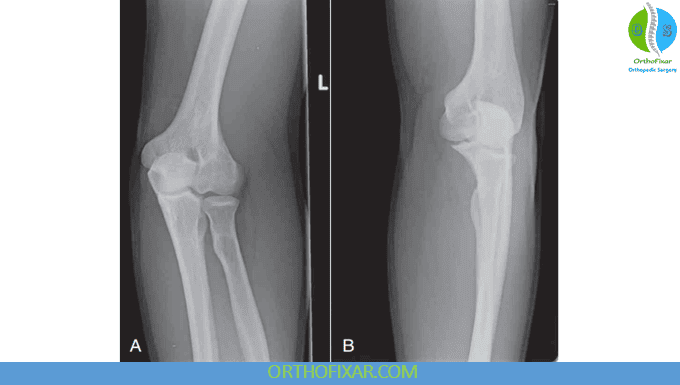

1. Elbow Anteroposterior (AP) View

Purpose: Provides a frontal view of the elbow joint, visualizing the distal humerus, proximal radius, and ulna.

Key points to assess:

- Bony landmarks: Epicondyles, trochlea, capitulum, radial head, radial tuberosity, coronoid process, and olecranon process.

- Always compare AP and lateral views—many injuries are missed on a single projection.